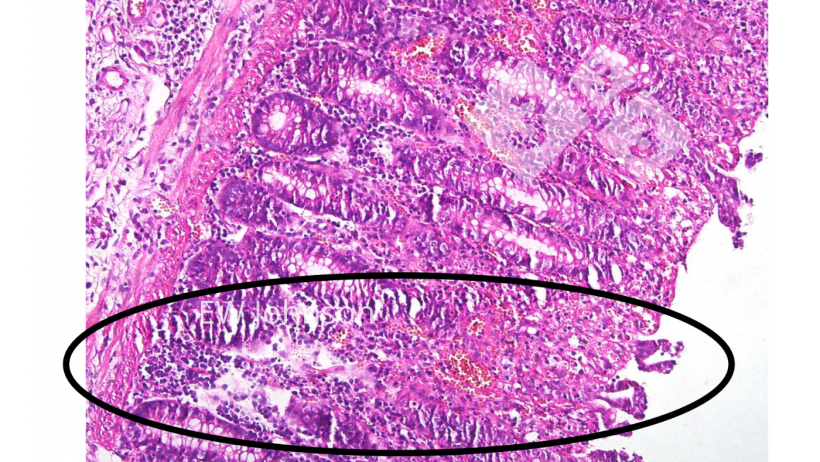

All'esame istopatologico si osserva una vasculite generalizzata con infarto, emorragia e trombosi in più organi, in particolare polmone, milza, linfonodi, reni, cervello e intestino. Vi è una massiccia distruzione linfoide nei linfonodi e nella milza e vacuolizzazione dei macrofagi alveolari. Sono frequenti necrosi e ulcerazioni dell'epitelio del colon (foto 4).

L'uso della istopatologia per verificare le lesioni croniche tipiche del vaccino con geni deleti può essere molto utile. I suini che hanno ricevuto tali vaccini contro la PSA spesso hanno lesioni vascolari fibrosanti e cicatriziali attive, inclusi trombi e infarti nell'intestino, nel fegato, nei tessuti linfoidi, nel cuore e nei reni. I linfonodi possono presentare aree emorragiche, con necrosi e distruzione dei linfociti e aree con fibrosi e cicatrici. I riproduttori vaccinati possono presentare ampie aree di necrosi polmonare e fibrosi che vengono spesso scambiate per App cronica. Il virus del vaccino potrebbe non uccidere il suino, ma il suino spesso non è in grado di eliminare il virus vaccinale.